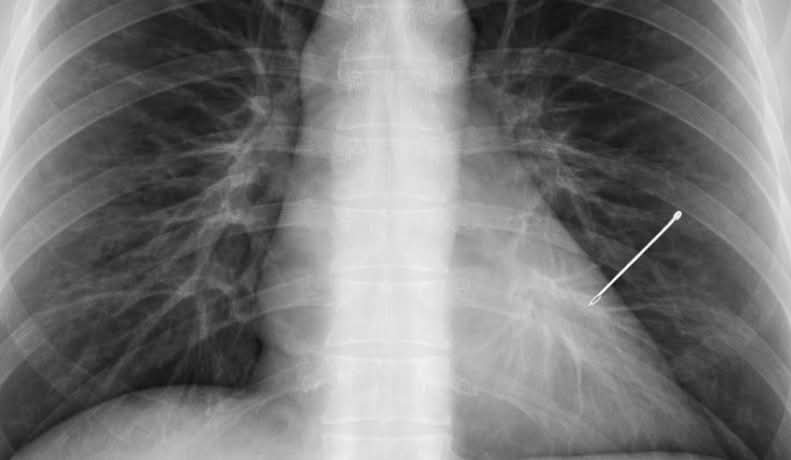

Un caz medical neobișnuit a fost identificat întâmplător la o femeie în vârstă de aproximativ 55 de ani, în timpul unui control radiologic de rutină. Investigația a evidențiat prezența unui ac de cusut în plămânul stâng, obiect care, potrivit estimărilor, ar fi rămas în organism timp de aproape trei decenii, conform informațiilor relatate de Adevărul.

Descoperirea l-a surprins pe medicul radiolog Nicolae Sârbu, care a declarat că, deși are peste 20 de ani de experiență în imagistică medicală, cazul i-a atras imediat atenția.

„Radiografia care m-a lăsat fără cuvinte după 20 de ani de experiență. În radiologie vezi de toate. După 20 de ani, crezi că nimic nu te mai poate surprinde. Și totuși. O pacientă de ~55 de ani vine pentru o radiografie pulmonară de rutină. Control periodic, nimic special. Pun radiografia pe ecran. Și îngheț. În plămânul stâng, clar vizibil, un ac de cusut”, a povestit medicul.

În timpul discuțiilor cu echipa medicală, pacienta a fost întrebată dacă își amintește vreun incident care ar putea explica prezența obiectului. Inițial surprinsă, aceasta a reacționat cu uimire și a povestit:

„Acum 30 de ani, când eram tânără, am înghițit un ac din greșeală. Îl țineam în gură când coasem. M-am speriat, dar nu m-a durut, nu am mers la urgență, mi-am zis că va trece… și am uitat de el. 30 de ani.”